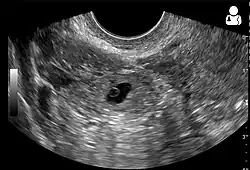

Transvaginal ultrasonography

An ultrasound showing a gestational sac with the fetal heart in the fallopian tube has a very high specificity for ectopic pregnancy. It involves a long, thin transducer, covered with the conducting gel and a plastic/latex sheath and inserted into the vagina.[38] Transvaginal ultrasonography has a sensitivity of at least 90% for ectopic pregnancy.[5] The diagnostic ultrasonographic finding in ectopic pregnancy is an adnexal mass that moves separately from the ovary. In around 60% of cases, it is an inhomogeneous or a noncystic adnexal mass, sometimes known as the "blob sign". It is generally spherical, but a more tubular appearance may be seen in the case of hematosalpinx. This sign has been estimated to have a sensitivity of 84% and a specificity of 99% in diagnosing ectopic pregnancy.[5] In the study estimating these values, the blob sign had a positive predictive value of 96% and a negative predictive value of 95%.[5] The visualization of an empty extrauterine gestational sac is sometimes known as the "bagel sign", and is present in around 20% of cases.[5] In another 20% of cases, there is visualization of a gestational sac containing a yolk sac or an embryo.[5] Ectopic pregnancies where there is visualization of cardiac activity are sometimes termed "viable ectopic".[5]

Transvaginal ultrasonography of an ectopic pregnancy, showing the field of view in the following image -

A "blob sign", which consists of the ectopic pregnancy. The ovary is distinguished from it by having follicles, whereof one is visible in the field. This patient had an intrauterine device (IUD) with progestogen, whose cross-section is visible in the field, leaving an ultrasound shadow distally to it. -

Ultrasound image showing an ectopic pregnancy where a gestational sac and fetus have been formed